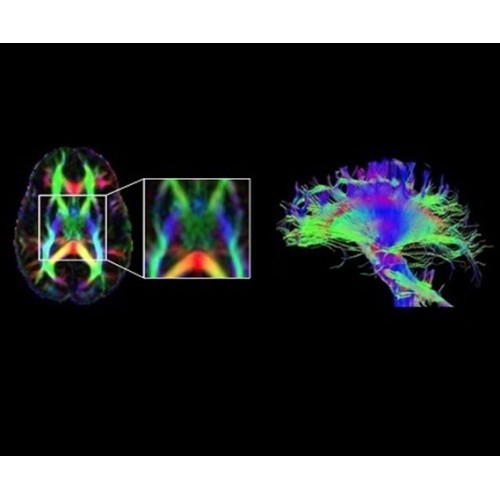

Новейшая платформа SIGNA Works4 повышает производительность ключевых технологий визуализации GE Healthcare. SIGNA Architect поставляется с предустановленными стандартными приложениями. Расширенные функции SIGNA Works с возможностью обновления позволят устанавливать новые приложения в соответствии с растущими потребностями вашей клинической практики.

Стандартный пакет приложений SIGNA Works позволит вам достичь желаемых результатов в клинической практике благодаря набору высокоэффективных средств визуализации. Программные приложения, входящие в состав данных клинических пакетов, включают широкий спектр контрастов, функции обработки 2D- и 3D-данных, а также возможность коррекции артефактов движения. SIGNA Works предоставляет набор инструментов, необходимых для проведения эффективного клинического исследования.

В системе SIGNA PET/MR есть все инструменты, необходимые для выявления маркеров разных заболеваний и для создания новых протоколов. ПЭТ/МРТ можно использовать совместно с мультиядерной спектроскопией в лаборатории in vivo для изучения быстрых биохимических процессов. Кроме того, PET ToolBox и набор инструментов Orchestra предоставляют персональный доступ к функциям реконструкции изображений для ПЭТ и МРТ, ускоряя и упрощая работу с необработанными данными.

• Специальный пакет приложений для измерения и сравнения объемных изображений ЦНС с нормами поможет вам в диагностике нейродегенеративных заболеваний, а дополнительные инструменты визуализации — в постановке точного диагноза с помощью бета-амилоидов и радиоизотопных маркеров ФДГ.